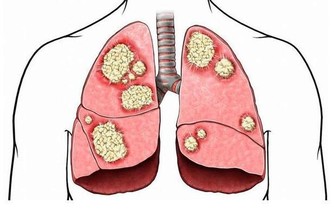

一旦患有糖尿病便無法通過治療康復,需要不停地通過藥物控制,在飲食方面尤其要多加注意。目前我國的糖尿病患者數量大約在一億左右,每年都有大量患者因糖尿病或併發症而喪失生命。那麼什麼是糖尿病呢?

首先我們來了解一下血糖和胰島素的關係。胰島素一種由胰腺分泌、能夠調節血糖的激素,並且可以幫助細胞將糖分轉化為能量。糖尿病是指患者的胰腺無法正常分泌胰島素,或是身體對胰島素無法做出正常反應。如果沒有外界干預,那麼患者不能分解攝入體內的糖分,血糖也會隨之大幅升高。

糖尿病的常見症狀包括,起夜次數頻繁、口乾、視力模糊、疲倦乏力、體重驟然下降、生殖器瘙癢、傷口所需的癒合時間過長等。這些都是身體無法正常分解血液中的葡萄糖所致。如果發現自己或家人朋友出現了類似狀況,要盡就醫治療。

按照導致血糖異常升高的方式不同,將糖尿病劃分成了兩種類型:一型糖尿病和二型糖尿病。前者是指患者無法正常產生胰島素,後者是指患者雖能自己分泌出胰島素,但身體對胰島素不敏感,無法正常分解代謝葡萄糖。其中二型糖尿病更為常見,佔比達到85%至95%。

那麼哪些人患有二型糖尿病的機率更高呢?據統計,多數患者是在四十歲左右被確診;不過近些年來糖尿病的平均發病年齡越來越低,內分泌專家認為這與肥胖症的流行密不可分。過度肥胖的人對胰島素的敏感性會逐漸減弱,體內的胰島素受體數量也會減少,久而久之便會誘發二型糖尿病,所以肥胖這個誘因是不可忽視的。無論體重是否在正常範圍之內,都要注重膳食營養均衡,堅持鍛煉身體,保持健康的體型,遠離各類疾病的困擾。